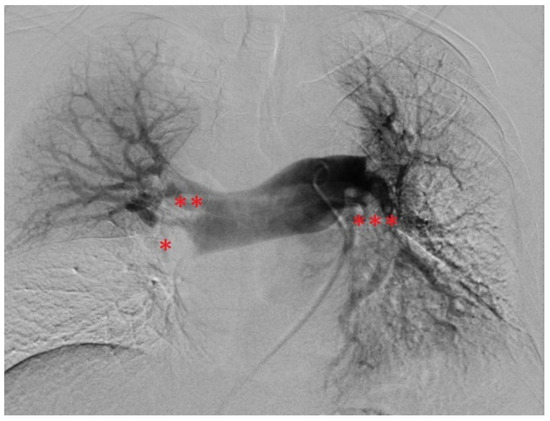

Elevation of high-sensitivity cardiac troponin T (43 ng/L) and NT-pro-BNP levels (3538 ng/L), as well as the hypoxemic respiratory failure found in the arterial blood gases (pO2: 67 mm Hg, pCO2: 24 mm Hg), underpinned the diagnosis. Pulmonary Embolism Severity Index (PESI) and simplified PESI (sPESI) scores were calculated to be 96 and 1, respectively [21,22]. From his PESI score, the patient was categorized as class III, revealing a moderate 30-day mortality risk (approximately 3–7%) [1,21]. Clinically, the patient was classified as intermediate–high risk [1]. Moreover, a DVT in the medial segment of the left posterior tibial vein was detected by compression ultrasonography. Based on this, he was anticoagulated therapeutically with unfractionated heparin by use of a perfusor. Interventional radiology was contacted with the request for endovascular mechanical thrombectomy, and the patient was transferred to the angiography suite. After bilateral ultrasound-guided access to the common femoral veins, thrombus in the pelvic veins and the inferior vena cava were ruled out using phlebography. The pulmonary trunk was selected using a 5F pigtail catheter, pulmonary artery pressures (PAP) were measured, and digital subtraction angiography (DSA) was performed (Figure 3). PAP measurements revealed elevated pressures with a mean PAP (mPAP) of 42 mm Hg. DSA confirmed CT findings with filling defects and a lack of contrasting of pulmonary parenchyma, especially in the right lower lobe. A stiff guidewire was navigated into the right lower lobe pulmonary artery. The 24F endovascular mechanical thrombectomy device (FlowTriever System) was advanced into the right lower lobar artery. Abundant embolic material was retrieved by repeated aspiration thrombectomy. In the left lung, initial attempts failed. By switching to a FlowTriever catheter containing disks for mechanical thrombus maceration and subsequently continuing aspiration thrombectomy, abundant embolic material was extracted from the left pulmonary arteries as well, particularly from the left lower lobar artery. The thrombi recovered from the pulmonary arteries are shown in Figure 4. Subsequently, a control DSA revealed open and well-perfused pulmonary arteries with only minimal residual thrombotic material (Figure 5). The mPAP immediately decreased by 28 mm Hg from an initial 42 to 14 mm Hg (systolic pulmonary artery pressure (sPAP): 65 → 28 mm Hg; diastolic pulmonary artery pressure: 29 → 6 mm Hg). After the intervention, the patient was hemodynamically stable and free of complaints, only experiencing slight remaining exertional dyspnea. From the patient’s perspective, the intervention was well tolerated. To minimize blood loss during the procedure, an autotransfusion system was used (FlowSaver, Inari Medical, Irvine, CA, USA). Moreover, it was carried out without complications, apart from a small postinterventional venous bleed at the access site in the right groin, which was managed by manual compression.

Figure 3. DSA findings before endovascular mechanical thrombectomy. Annotation: right interlobar artery (*) appears truncated with no parenchymal contrasting of the right lower lobe. There are significant filling defects in the right superior trunk (**), the left interlobar artery (***) and the left apical segmental arteries, also with a lack of contrasting of the corresponding pulmonary parenchyma. DSA, digital subtraction angiography.

Figure 5. DSA findings after endovascular mechanical thrombectomy. Annotation: Near-complete contrasting of the right interlobar artery (*), the right superior trunk (**), left interlobar artery (***) and left apical segmental arteries with only small remaining filling defects corresponding to small residual thrombi. DSA, digital subtraction angiography.